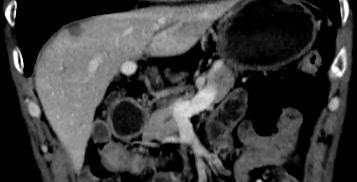

患者 李某某,男,65岁。2019-08外院胃镜提示:贲门巨大溃疡性病变。08-29我院病理会诊(H191689):贲门中分化腺癌。免疫组化:HER2(3+),Ki-67(+,约30%)。08-30胸腹部CT扫描:示胃贲门及小弯病灶伴肝脏、肝门区、肝胃间隙多发淋巴结转移,CEA、CA199明显升高。08-29就诊我科,确定发生了重度营养不良(PG-SGA评级C级)。诊断:贲门癌复发,肝脏、腹腔淋巴结多发转移( IV期, HER2阳性);重度营养不良PG-SGA C级。

基线评估